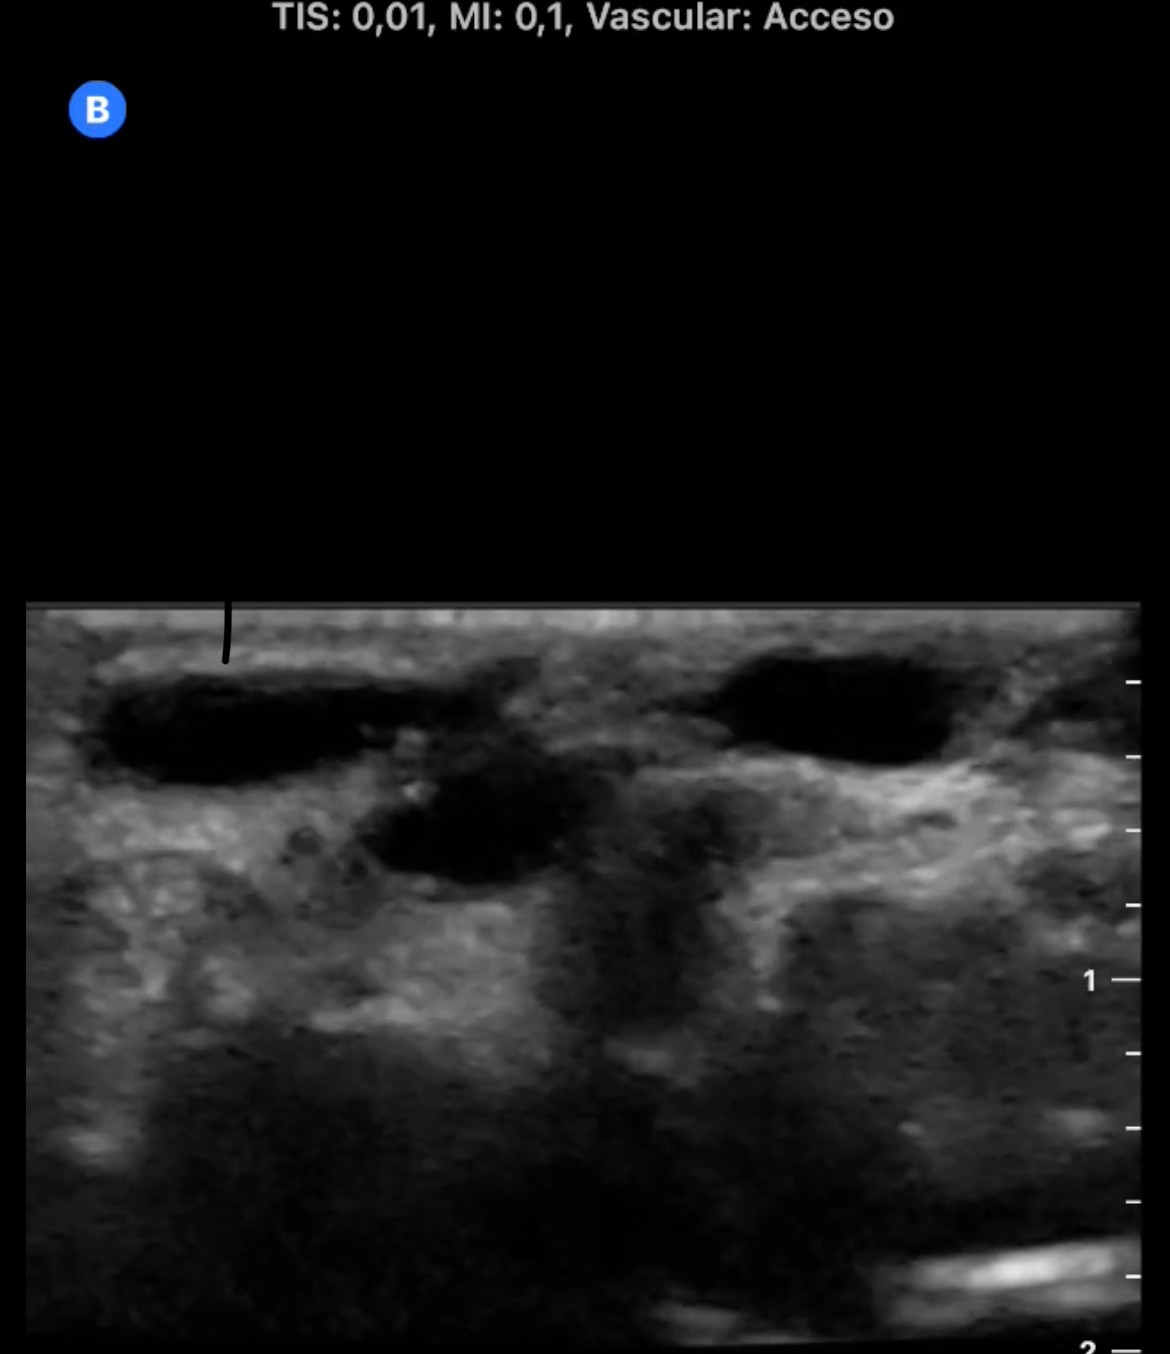

En la cara palmar de la muñeca derecha se aprecia un aumento de tamaño de las venas superficiales con flujo Doppler color en su interior. En arteria radial se observa flujo muy turbulento con comunicación de arteria radial con una vena superficial del antebrazo.

El diagnóstico diferencial incluía además de la fístula arteriovenosa, el pseudoaneurisma y la trombosis.